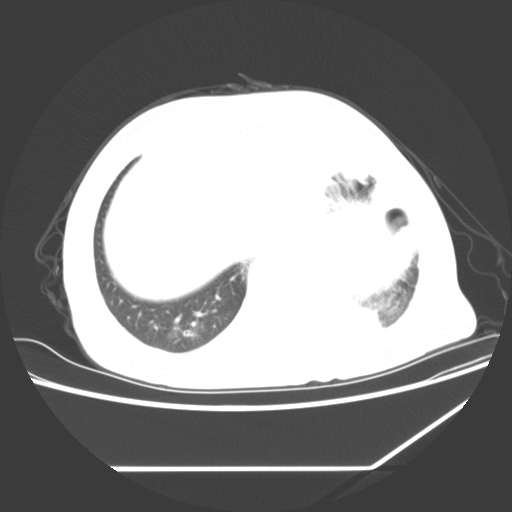

标题: CT25393:病人45岁,咳嗽,吐黄痰带血丝,发热,胸闷月余

1、左肺中央型肺癌并双肺弥漫性转移   2、双肺部感染    3、肺大泡     4、左侧胸腔积液

双侧肺弥漫性病变,可见“空泡征”及“蜂窝征”,考虑肺泡癌可能性大,左侧胸腔积液,考虑胸膜受累可能!

1)不排除肺泡癌可能。2)左侧胸腔积液。